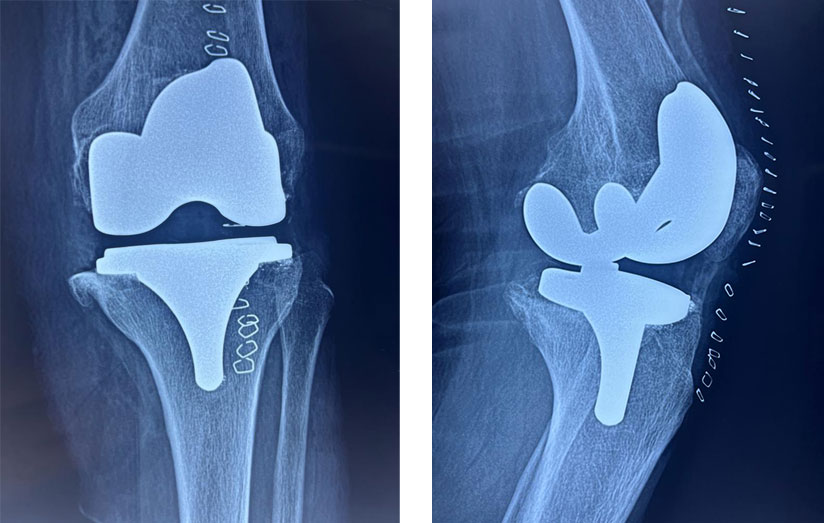

A diferencia del procedimiento tradicional, el sistema robótico permite realizar cortes más precisos en el hueso mediante un software que guía al cirujano en tiempo real.

Esto ayuda a colocar los implantes con mayor exactitud y a lograr una alineación personalizada, ajustada a la anatomía de cada paciente.